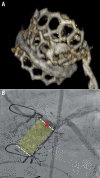

Transcatheter aortic valve implantation (TAVI) within failed bioprosthetic surgical aortic valves (valve-in-valve TAVI) has become an established procedure, currently approved for patients deemed at high risk for repeat aortic valve intervention. Although less invasive than surgical reoperation, challenges of valve-in-valve treatment include higher rates of malposition, prosthesis-patient mismatch and coronary obstruction. Thus, optimal patient selection and preprocedural planning is of the utmost importance to minimise the risk of these complications. In this review article we provide a fully illustrated overview of the most significant periprocedural operative considerations for valve-in-valve TAVI.